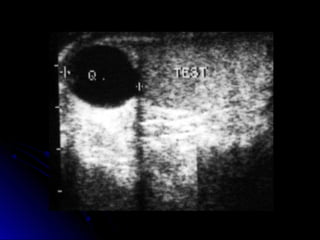

Se detectan como lesiones anecoicas, bienSe detectan como lesiones anecoicas, bien

definidas con refuerzo acústico posterior.definidas con refuerzo acústico posterior.